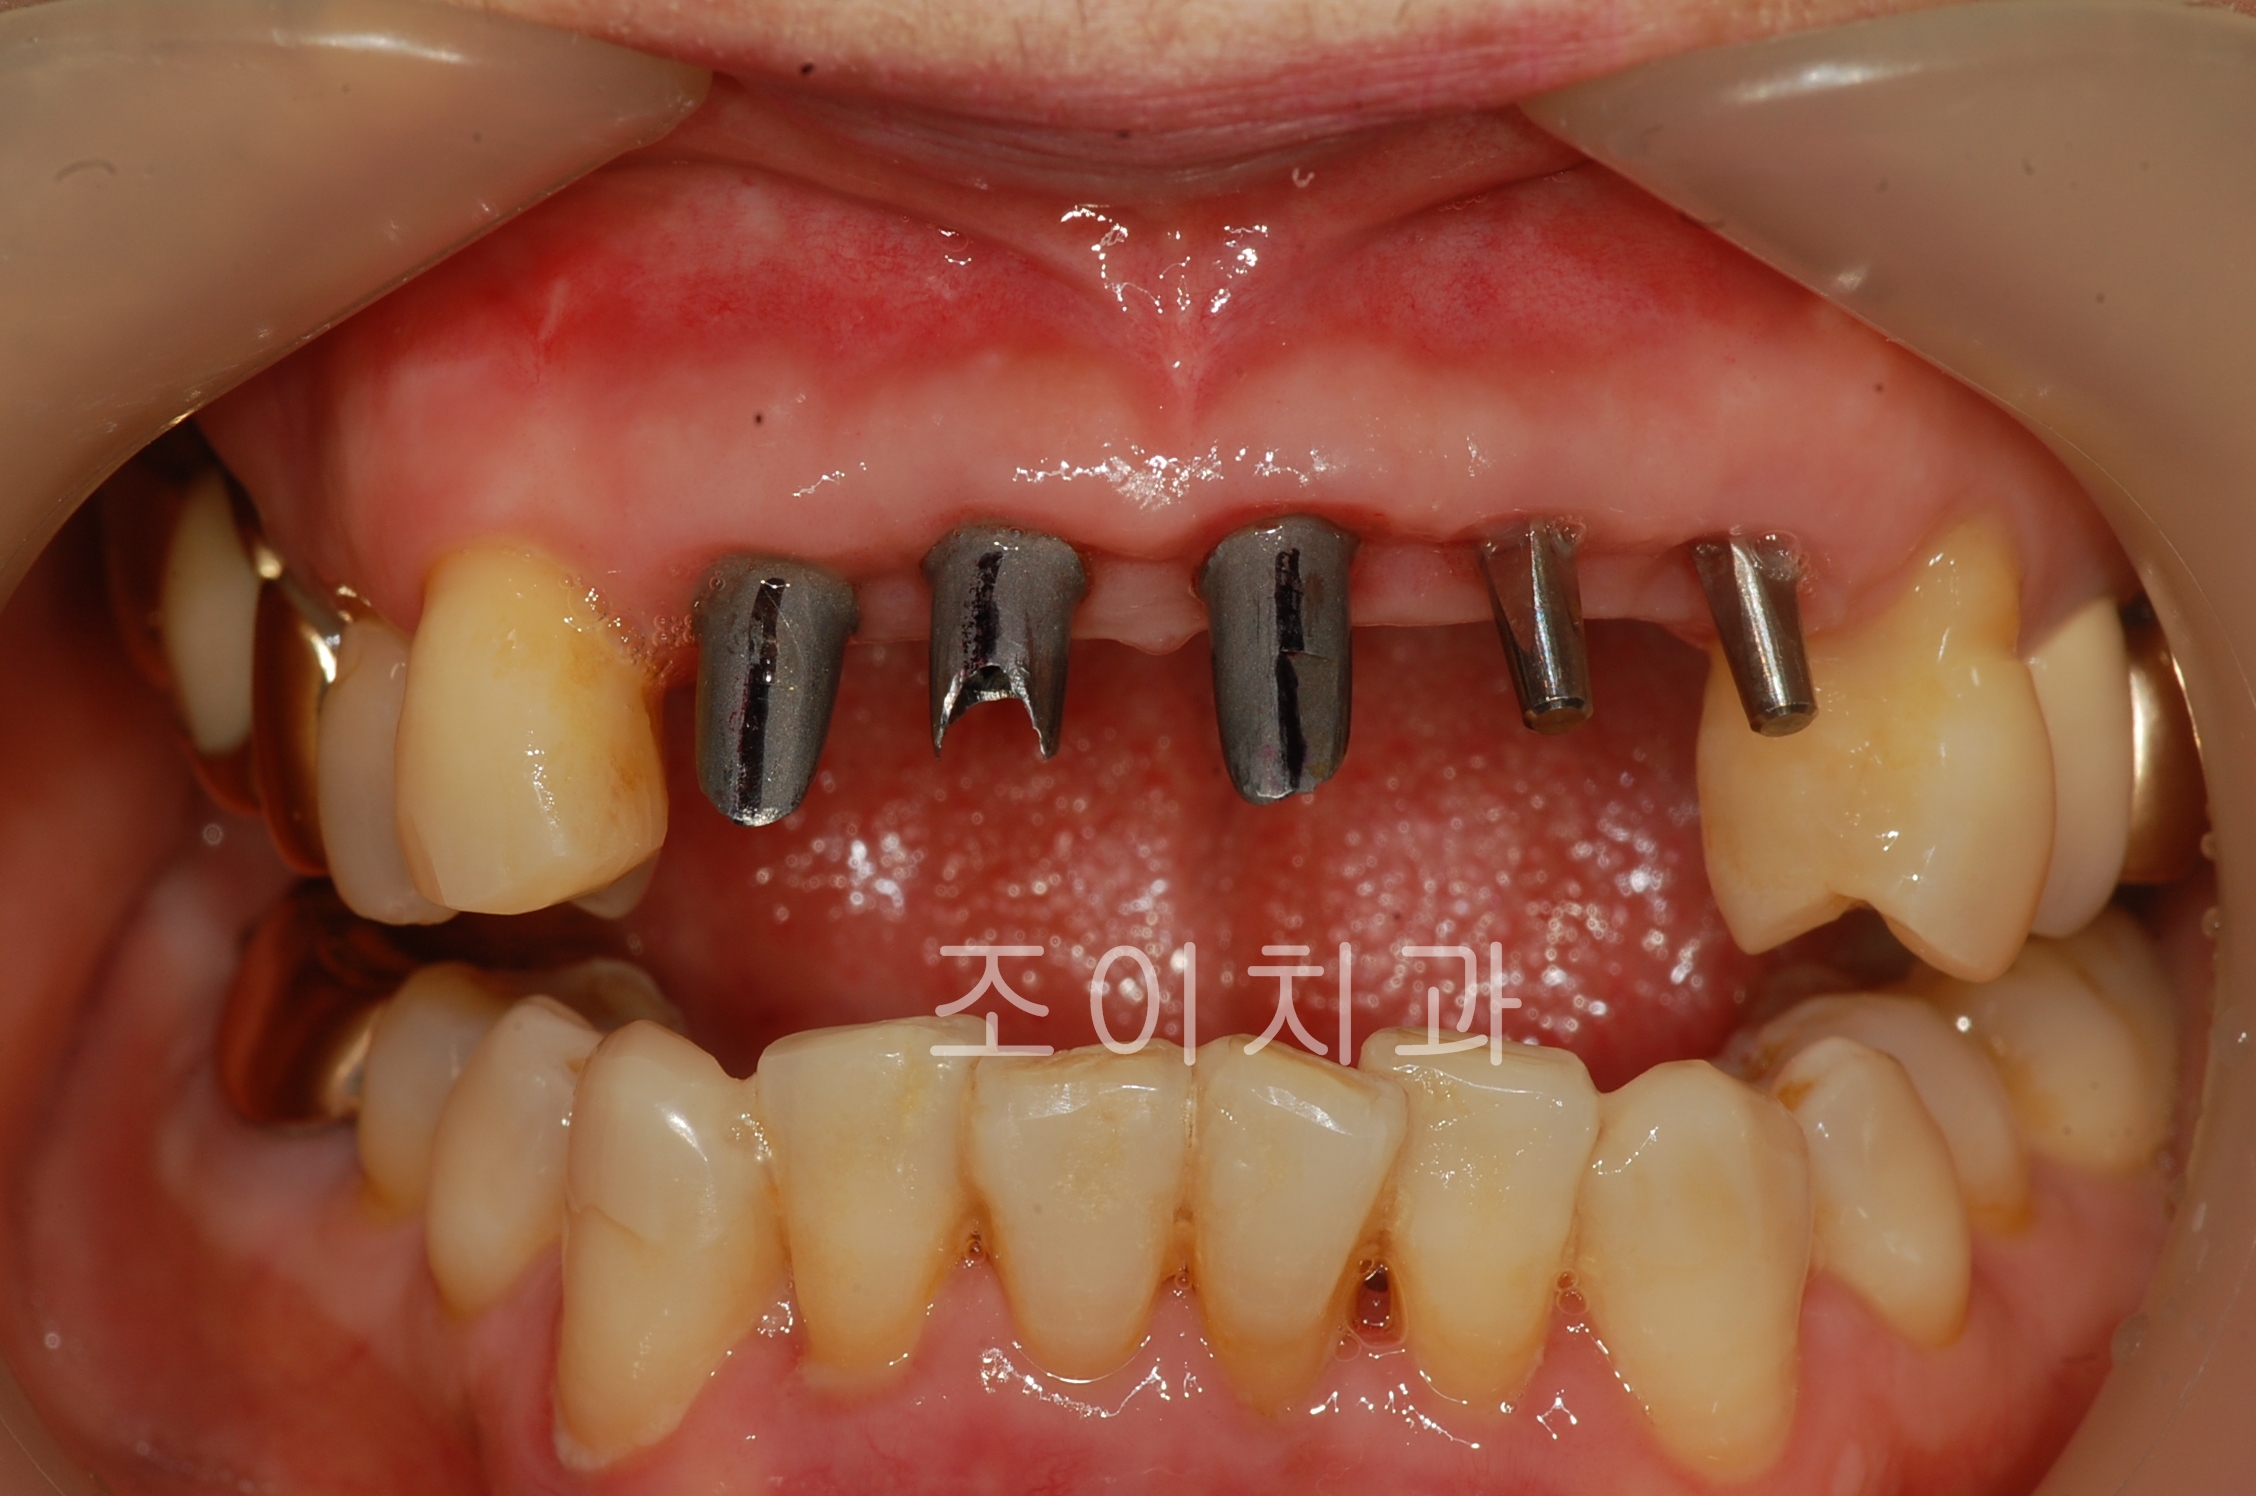

[임플란트] 제목 : 상악전치

임플란트 보철